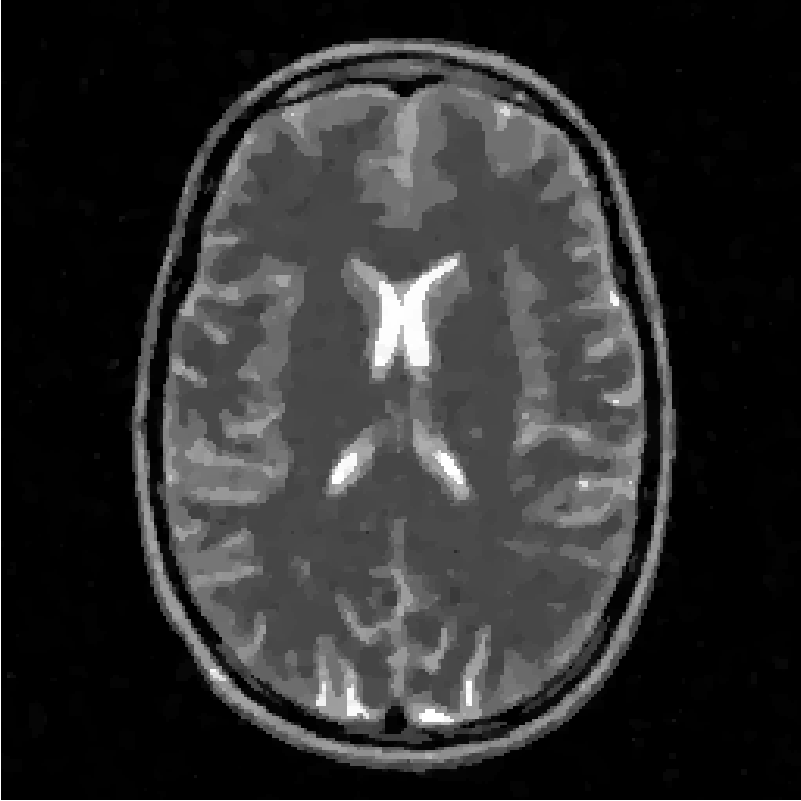

Concerning the real MRI data we compare IL and FNCR algorithms in the reconstructions of the brain image (T3 test), represented in figure 8. We report in table 6 the results obtained by reconstructing the noiseless data undersampled by , , masks.

From the table, we see that FNCR always outperforms IL.

In figure 10 we show the FCNR and IL reconstructions in case of mask and .

Finally in figure 9

we plot the reconstructed rows corresponding to the largest error (200-th row) for the true image and

the FNCR reconstruction (Figure 9(a)) and for the true image and

IL reconstruction (Figure 9(b)).

We observe that FNCR better fits the corresponding row of the original image.